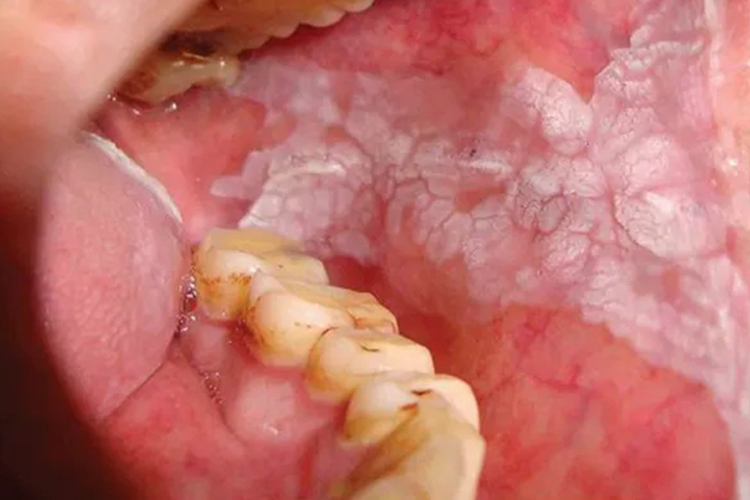

口腔黏膜网状白纹呈灰白或浅白等,不高出或微高于黏膜平面,触之柔软,多无自觉症状。

口腔白色角化病可发生在口内与刺激因素有关的任何部位,以颊、唇和腭部多见。为灰白色、浅白或乳白色边界不清的斑块或斑片,可呈网格纹状分布,不高出于或微高于黏膜表面,表面光滑无结节,触之柔软而无自觉症状。

患者一般无自觉症状,或自觉粗糙、木涩等。口腔黏膜的损害形态多样,可表现为网状、斑块状、皱纹纸状、颗粒状、疣状、溃疡状白斑。牙龈、颊黏膜咬合线及舌部都是好发部位。